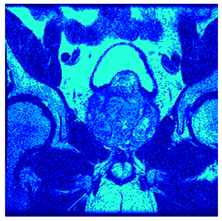

| Image | nt = 3 | nt = 4 | nt = 5 | nt = 8 |

|---|---|---|---|---|

| 1 | ![]() | ![]() | ![]() | ![]() |

| 2 | ![]() | ![]() | ![]() | ![]() |

| 3 | ![]() | ![]() | ![]() | ![]() |

| 4 | ![]() | ![]() | ![]() | ![]() |

| 5 | ![]() | ![]() | ![]() | ![]() |

| 6 | ![]() | ![]() | ![]() | ![]() |

| 7 | ![]() | ![]() | ![]() | ![]() |

| 8 | ![]() | ![]() | ![]() | ![]() |

| 9 | ![]() | ![]() | ![]() | ![]() |

| 10 | ![]() | ![]() | ![]() | ![]() |

| 11 | ![]() | ![]() | ![]() | ![]() |